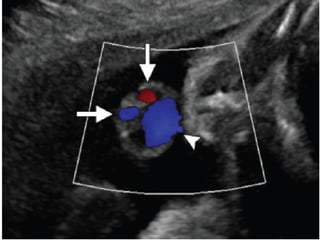

ANORMALIDADES VASCULARES:

PERSISTENCIA DE LA VENA UMBILICAL DERECHA

0.1 a 0.3%

- SITUS INVERSUS Y HETEROTAXIA

- GU, GI, cardiaco y esquelético.

ANORMALIDADES VASCULARES: PERSISTENCIA DELA VENA UMBILICAL DERECHA 0.1 a 0.3% - SITUS INVERSUS Y HETEROTAXIA - GU, GI, cardiaco y esquelético.